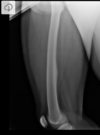

Cisto ósseo simples com fratura

Lesão litica unicameral.

Localização: úmero proximal e femur (< 20 anos) ou calcâneo, talus, ileo (> 20 anos).

Se fratura: Sinal do fragmento caído.